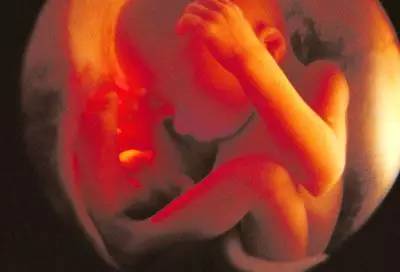

第八个月

胎宝宝身长约40cm,体重约1800g,此时的胎宝宝已经充满整个子宫,生长迅速,活动空间变小,皮下逐渐长出脂肪,大脑迅速发育,眼睛开闭自由,可以辨认和追踪光源。